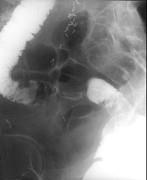

问题 女,50岁,便血10余年,加重1年(连续出血),近2个月大便时肛门常滴鲜血,量较多,X线检查如图,最可能的诊断是()

选项 A.直肠癌 B.直肠绒毛状腺瘤 C.直肠淋巴瘤 D.直肠转移瘤 E.直肠结核

答案 B